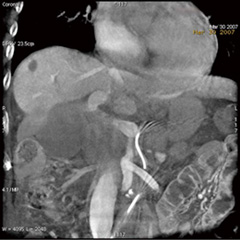

■ 高コントラスト&低アーチファクトな3D/CBCT

Innova3D+は,Innova3Dの回転速度を落として,収集フレーム総数を増やすことにより,軟部組織の観察により適した画像を収集するアプリケーションである。3D/CBCT画像が広範囲に撮影できるだけでなく,スライス厚を薄くした状態においてもきわめてアーチファクトが少なく,高コントラストな画像を得ることが可能である。肝細胞がんに対する肝動脈塞栓術の際など,DSAでは診断困難な肝動脈領域の小さな濃染像の検出にも有用である(図3)。

図3 CBCT